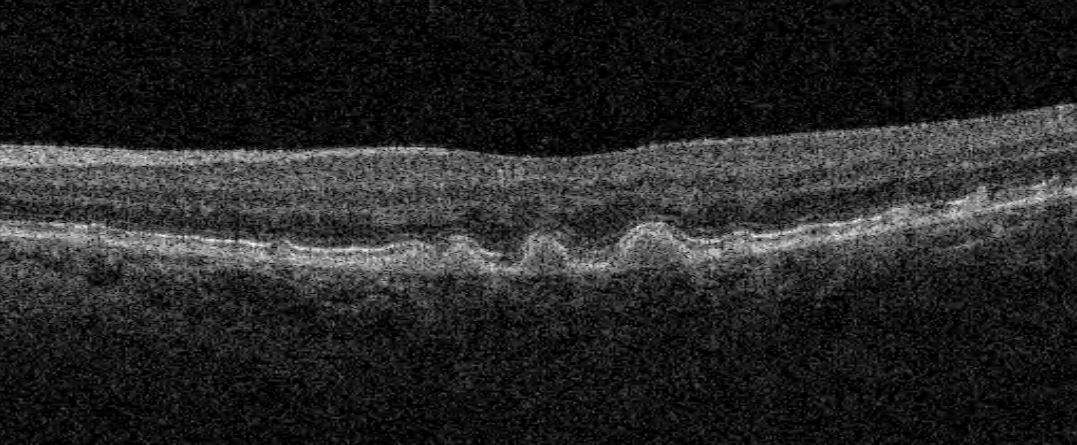

Technology is rapidly changing the eye care industry. We now have access to an amazing array of instruments which allow us to perform advanced testing and see layers of the retina in-situ.

At Eyedeal Optometrist we are proud to provide our patients with the latest technologies for earlier detection of eye diseases.

Macular degeneration (AMD) is a disease that affects the central vision of people over 50 years of age. It is the leading cause of visual impairment in Australia.

Diabetes can affect the small blood vessels at the back of the eye, leading to bleeding and scarring in the retina and possible irreversible vision loss.